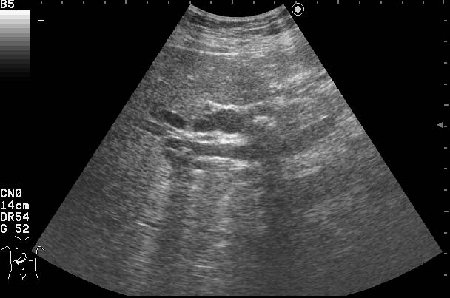

Сонограммы холедоха:

- Продольный скан холедоха